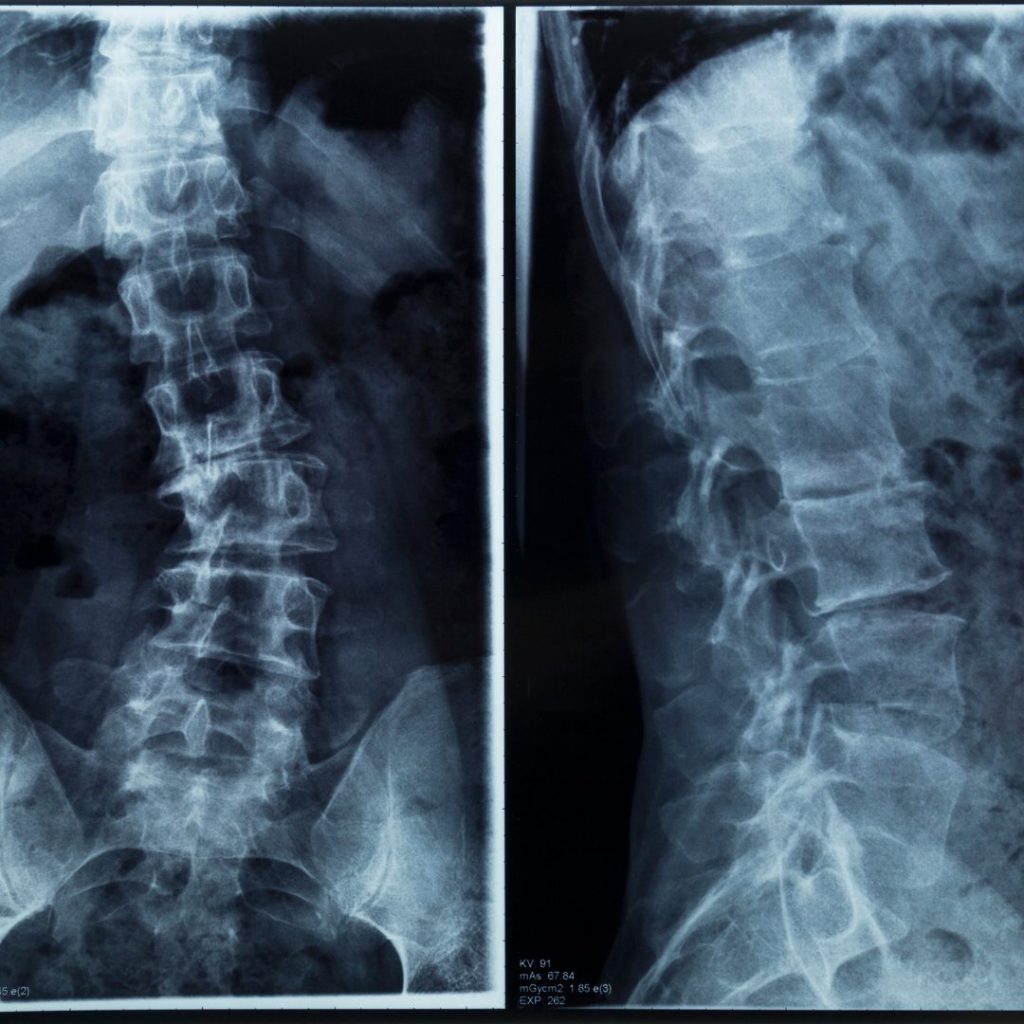

Have you ever had an x-ray and noticed an empty black space between each vertebra throughout the spine? Don’t worry, it’s not empty spaces. That is where each disc resides at each level. The intervertebral disc plays an extremely crucial role in movement and spine protection. Unfortunately, the disc can become damaged, leaving individuals with…

What do you think of when you see the human spine? Bones? Skeleton? X-rays? Halloween? Now what if you ask a chiropractor that exact same question? In this week’s blog, we will talk about the purpose of the human spine, each section of the spine and how to keep the spine in good health. The…

The majority of people in this world will break at least one bone somewhere in the body during their lifetimes. How do doctors look for broken bones? That’s right, x-ray. X-ray is a form of diagnostic imaging used to look for several different pathologies as well as fractures. X-ray was discovered in November 1895, 2-months…